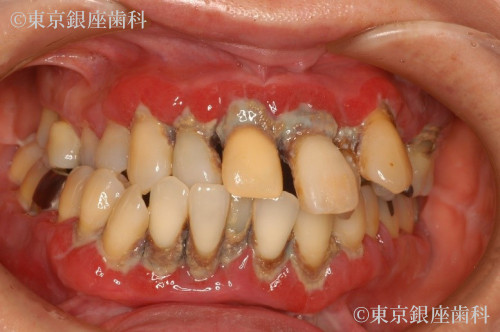

歯の揺れがひどくまともな食事がとれず口腔内の悩みにより鬱傾向。

歯の揺れがひどくまともな食事がとれない。

歯の見た目や口臭が気になり引きこもりがちになったがカウンセリングにてワンデイインプラントについて理解し前向きに治療に取り組むようになった。

歯周病の進行により歯に動揺があり長期の保存が難しく、臼歯の欠損で咬み合わせが下がって前歯部への負担が大きくなっているため全顎的な治療が必要と判断し上下顎でワンデイインプラントを行うことにした。